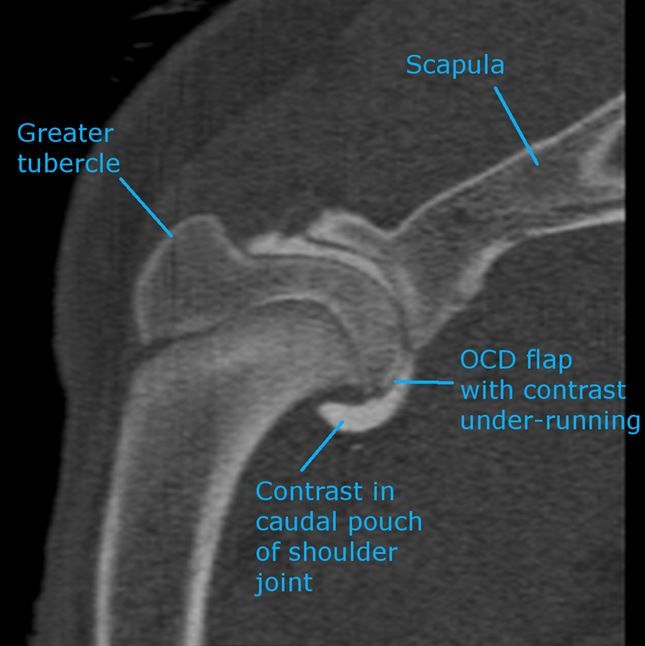

CT arthrogram was performed and was diagnostic of osteochondritis dissecans of the humeral head. A joint mouse was also visible within the shoulder joint.

Cartilage flap in situ on the caudal humeral head